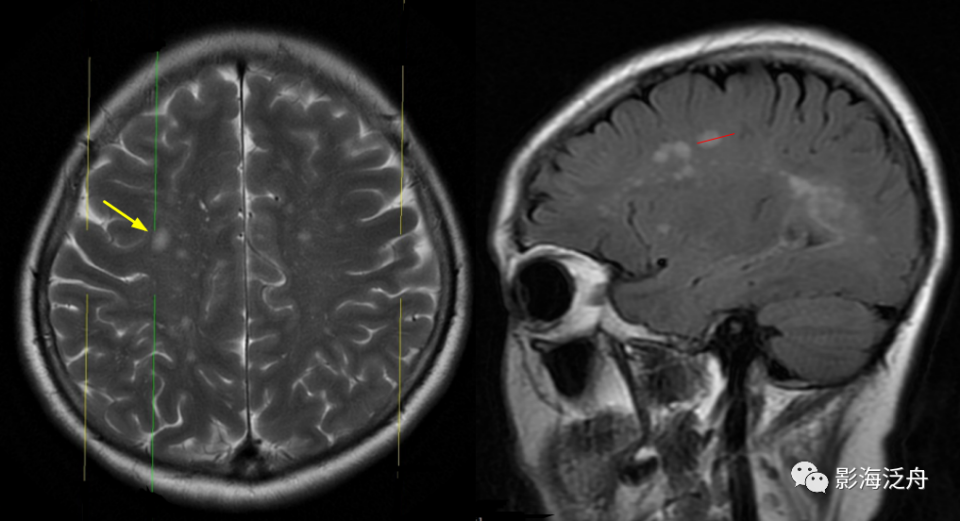

VR间隙(Virchow-Robin)又称血管周围间隙,是脑穿支血管(动脉、静脉)由蛛网膜下腔进入脑实质时,邻近软脑膜内陷在小血管周围(不包括毛细血管)形成的介于两层软脑膜之间的间隙,通常情况下MR图像上不可见,但在少数正常人及多数老年人可以见到,称之为VR间隙扩大,多对称性分布于半卵圆中心、放射冠、基底节下部、海马、中脑大脑脚、中脑脑桥交界区及额顶叶皮层下白质区等。

I型-基底节型:扩大VR腔隙呈对称性分布于双侧基底节区(红箭),左侧较大呈圆形,右侧较小呈斑点状。基底节型扩大VR腔隙好发于基底节下部,尤其是前联合层面(黄箭所指为前联合)。